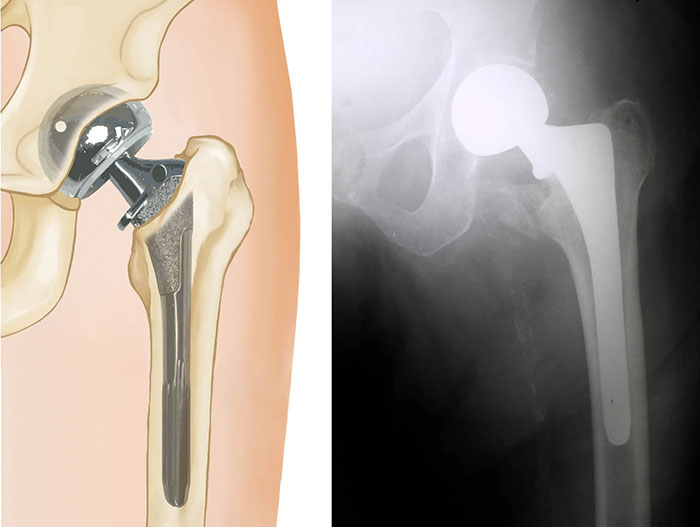

• For elderly patients, a hemi-arthroplasty, or partial hip replacement, is typically the treatment of choice.

• In properly selected patients, there may be a benefit to total hip replacement (at the risk of increasing complications). Total hip replacement may also be considered in younger, more active patients.

partial hip replacement

Treatment of a displaced femoral neck fracture with a partial hip replacement.

X-ray courtesy of Stuart J. Fischer, MD, FAAOS